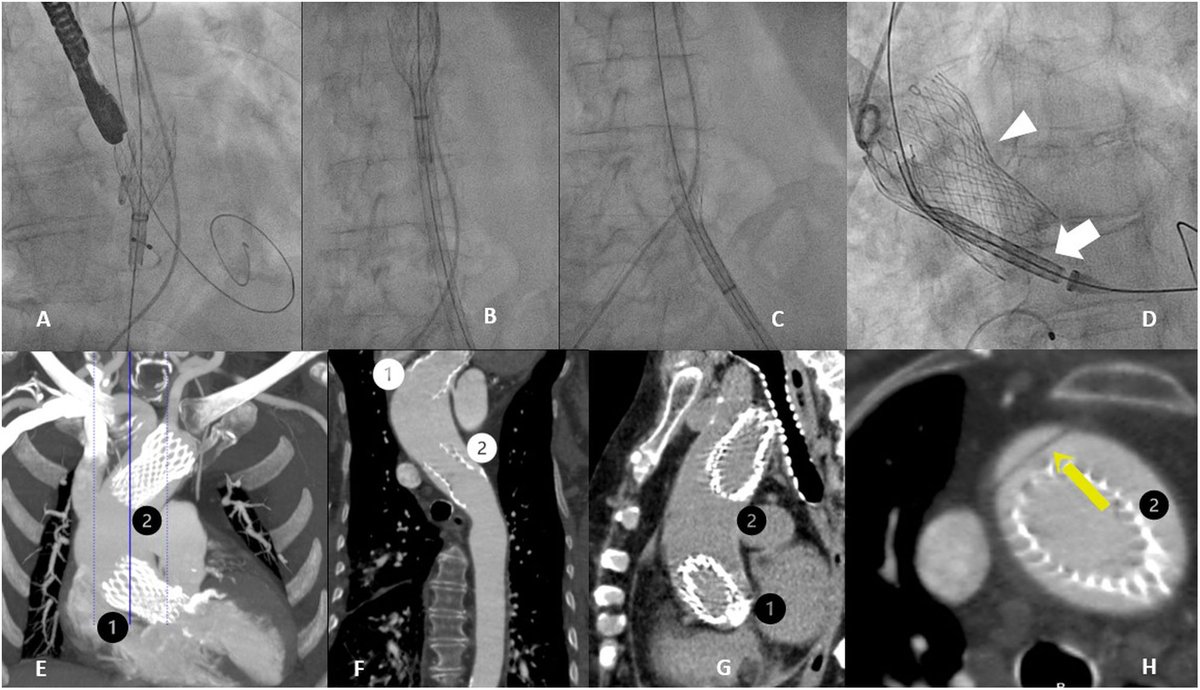

TCMD: herramienta clave en la evaluación pre-TAVI. Este artículo de la @RevistaRADIOLOGIA destaca la importancia de la tomografía computarizada multidetector (TCMD) en la identificación de factores de riesgo y posibles complicaciones antes del procedimiento TAVI. Una lectura